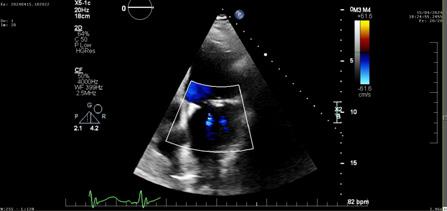

Cazuri disperate în chirurgia cardiacă –atunci când abordul minim invaziv este soluția

Dr. Ion Iovu, Prof. Univ. Dr. Lucian Dorobanțu, Dr. Andreea Bogdan, Dr. Ioana Băjenaru, Dr. Oana Ioniță, Dr. Mădălina Cojocaru, Dr. Toma Iosifescu, Conf. Dr. Cătălin Badiu, Dr. Alexandru Vasilescu